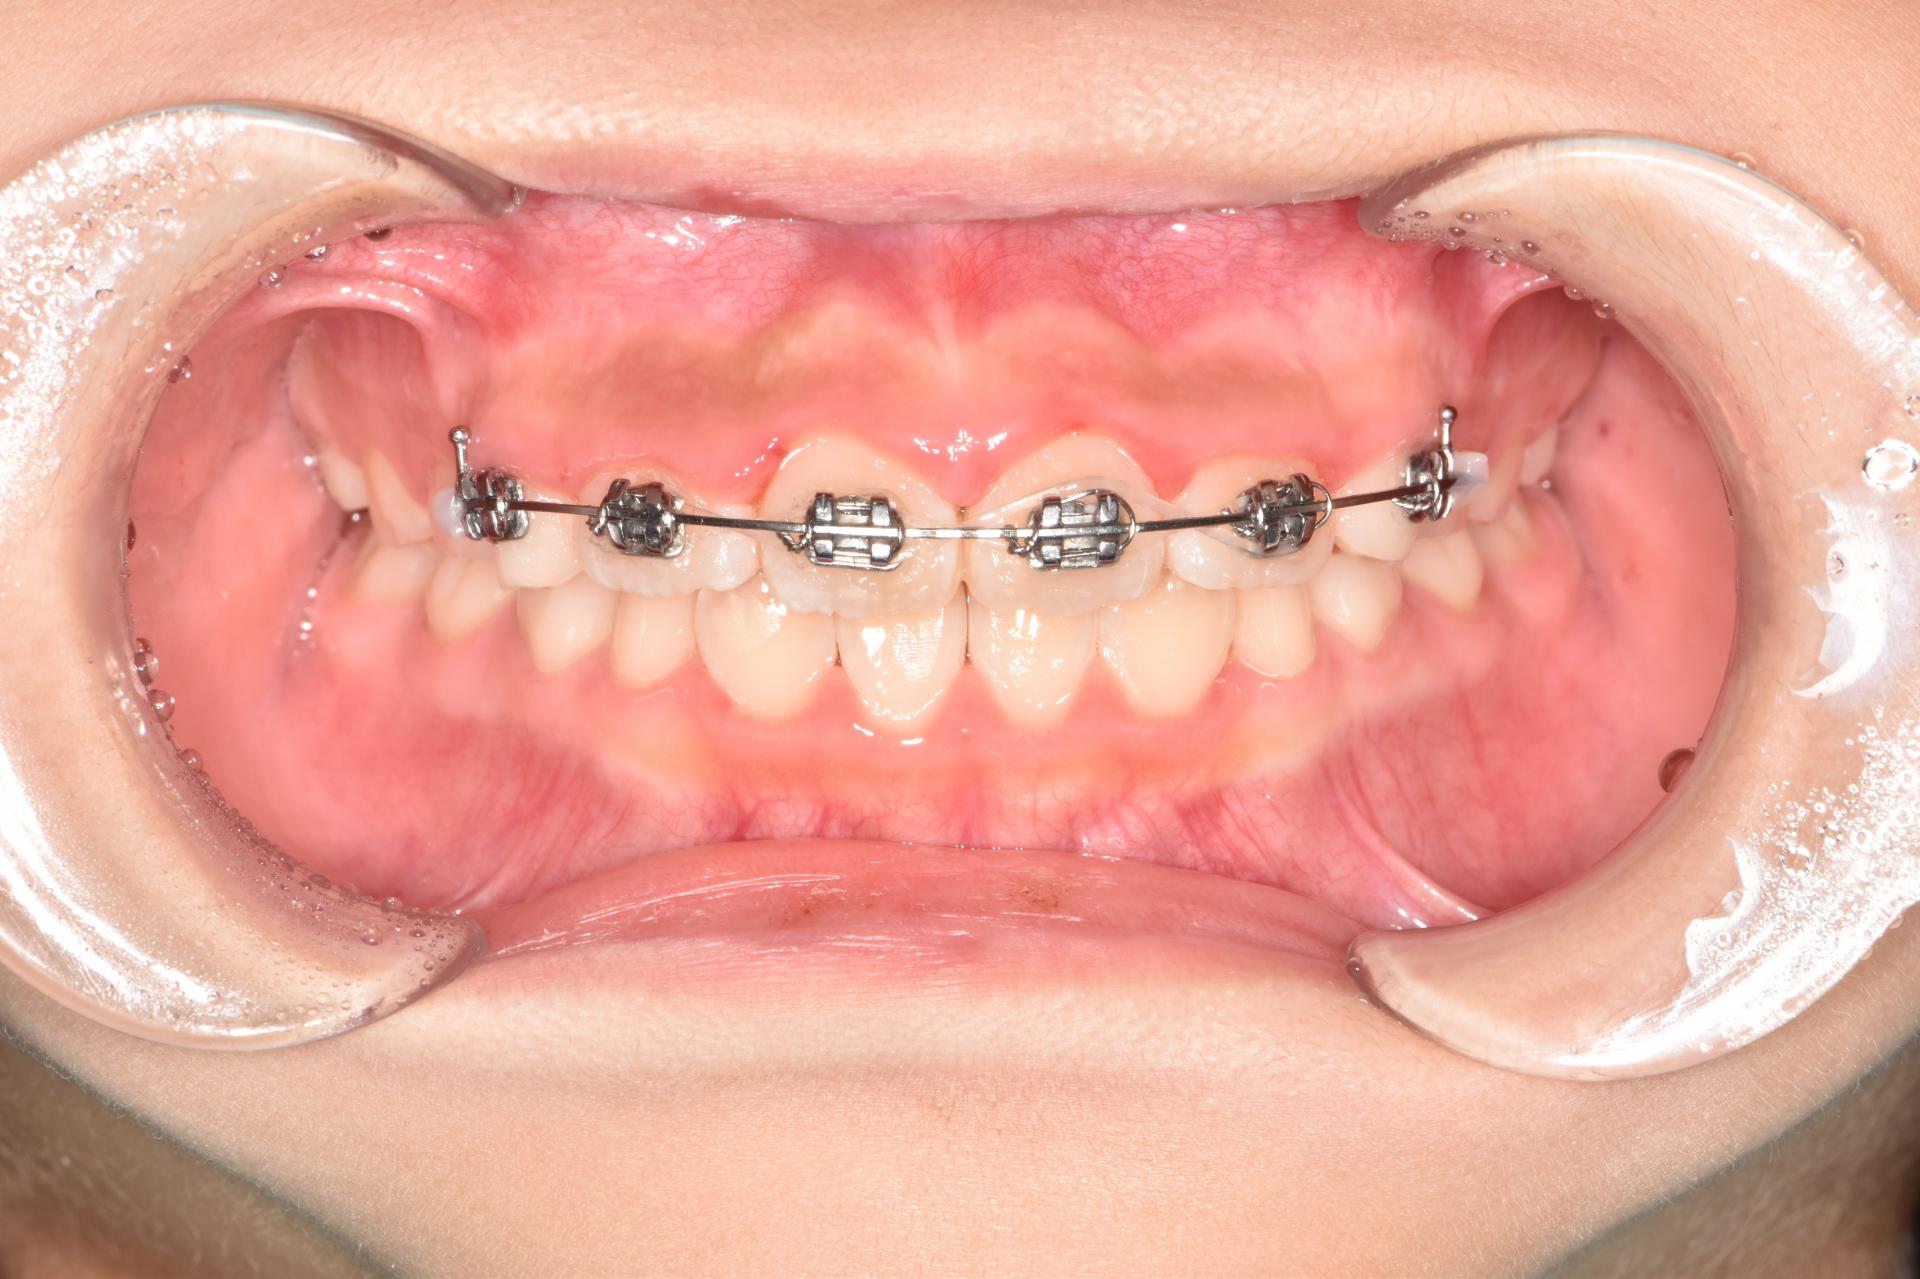

초진상태 입니다. 치아가 나올 공간이 부족하여 치아가 회전되어 삐뚤빼뚤나오고 앞니가 튀어나와있습니다.

예전부터 많이 하던 교정으로, 악궁확장장치(뺐다꼈다 하는 장치)로 악궁을 넓혀 공간을 만들고 삐뚤빼뚤한 치아는 브라켓 철사교정으로 예쁘게 해주었습니다.